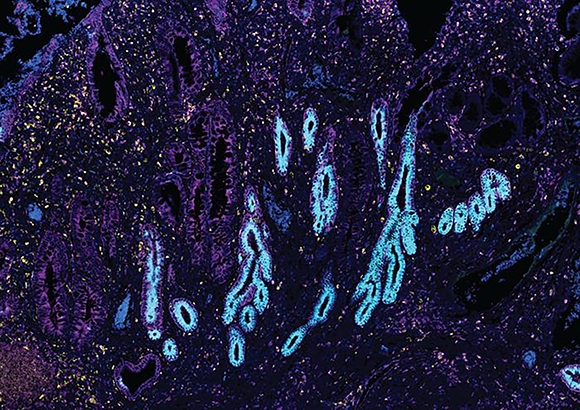

בין התאים של אנשים בריאים לעומת מידע על 1.6 מיליון תאים של חולי מחלות מעיים דוגמת קרוהן, צליאק, כיבים וסרטן. תאי מעי של חולה במחלת מעי דלקתית | מתוך המאמר A. Oliver, N. Huang, R. Li, et al. 2024

האטלסים של הרקמות השונות צפויים לשמש בסיס להשוואה עבור מחקרים עתידיים. תאי מעי של חולה במחלת מעי דלקתית | מתוך המאמר A. Oliver, N. Huang, R. Li, et al. 2024